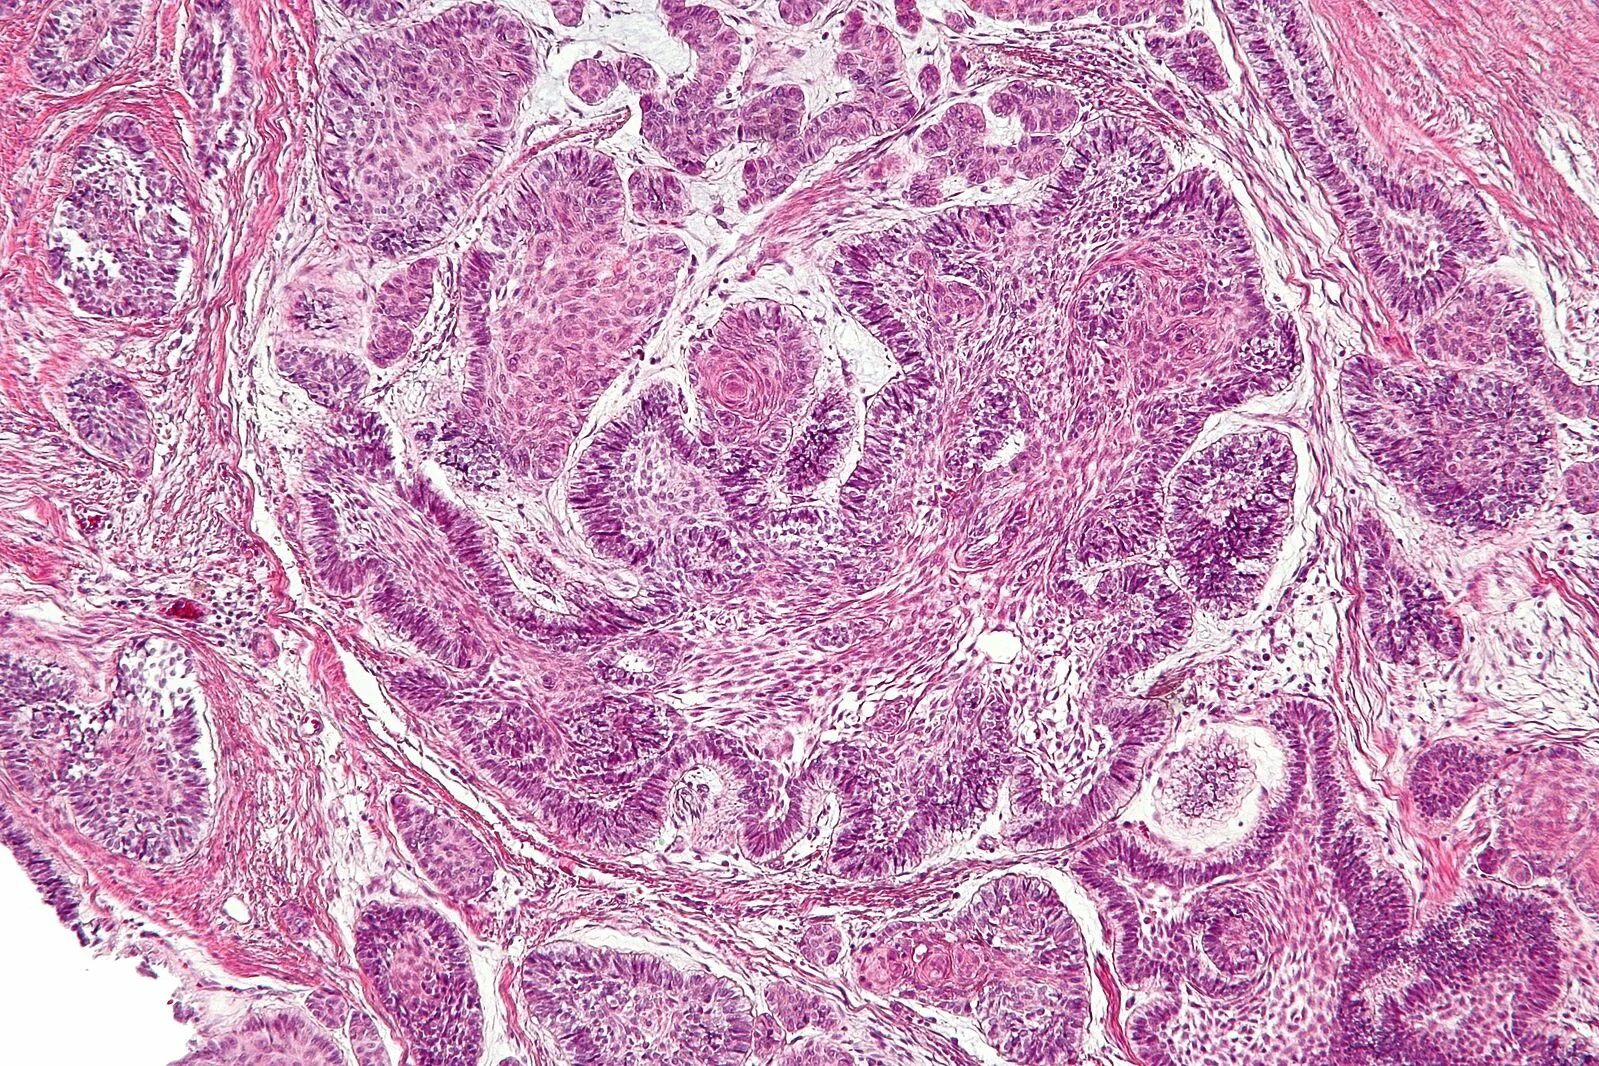

Гистология фиброзные фрагменты